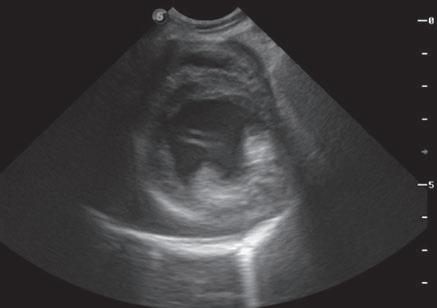

La responsabilidad de los artículos, reportajes, comunicados, etc. recae exclusivamente sobre sus autores. El editor sólo se responsabiliza de sus artículos o editoriales. La ciencia veterinaria está sometida a constantes cambios. Así pues es responsabilidad ineludible del veterinario clínico, basándose en su experiencia profesional, el correcto diagnóstico de los problemas y su tratamiento. Ni el editor, ni los autores asumen responsabilidad alguna por los daños y perjuicios, que pudieran generarse, cualquiera que sea su naturaleza, como consecuencia del uso de los datos e información contenidos en esta revista. De acuerdo con la normativa vigente en materia de protección de datos Grupo Asís Biomedia, SL., es responsable del tratamiento de sus datos personales con la finalidad de enviarle comunicaciones postales de nuestras revistas especializadas, así como otras comunicaciones comerciales o informativas relativas a nuestras actividades, publicaciones y servicios, o de terceros que puedan resultar de su interés en base a su consentimiento. Para ello, Grupo Asís podrá ceder sus datos a terceros proveedores de servicios de mensajería. Podrá revocar su consentimiento, así como ejercer sus derechos de acceso, rectificación, supresión, oposición, limitación y portabilidad enviando un correo electrónico a protecciondatos@grupoasis.com, o una comunicación escrita a Grupo Asís en Centro Empresarial El Trovador, planta 8, oficina I, Plaza Antonio Beltrán Martínez 1, 50002, Zaragoza (España), aportando fotocopia de su DNI o documento identificativo sustitutorio e identificándose como suscriptor de la revista. Asimismo, si considera que sus datos han sido tratados de forma inadecuada,